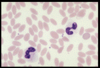

Name this WBC

Neutrophil